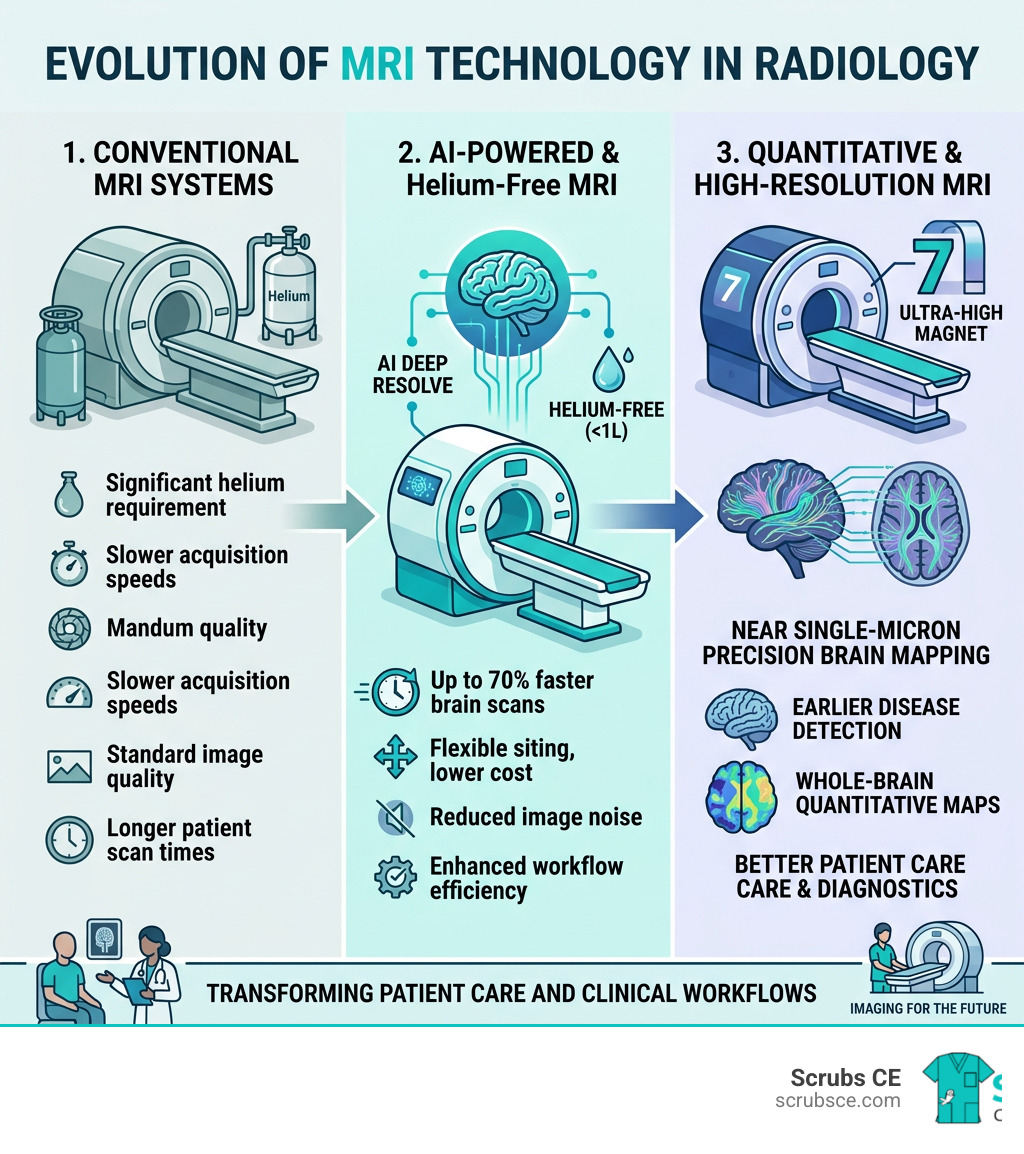

New MRI technology is advancing faster than ever — reshaping how radiologic technologists work, how patients experience scans, and how clinicians diagnose disease.

Here is a quick overview of the biggest breakthroughs happening right now:

| Technology | What It Does | Key Benefit |

|---|---|---|

| AI Deep Resolve | Reduces noise, speeds up scans | Up to 70% faster brain scans |

| Helium-free MRI (0.55T/1.5T) | Operates with just 0.7L of helium | Lower cost, flexible siting |

| Connectome 2.0 | Maps brain fibers at near single-micron precision | Noninvasive microscopic brain imaging |

| 7T MRI + MR Fingerprinting | Whole-brain quantitative maps at 360-micron resolution | Earlier detection of brain disease |

| Low-field + Xenon gas MRI | Visualizes lung airways without radiation | Better COPD and respiratory diagnostics |

| New contrast agents (Gadopiclenol) | High relaxivity at half the gadolinium dose | Safer, sharper contrast imaging |

AI-Driven Efficiency and the Rise of New MRI Technology

If you’ve been in the scan room lately, you know that the “clunk-clunk-clunk” of the gradients hasn’t changed much, but what’s happening behind the scenes in the computer room certainly has. Artificial Intelligence (AI) is no longer a futuristic concept; it is the current engine driving New MRI technology toward unprecedented efficiency.

The star of the show right now is Deep Resolve, an AI-powered image reconstruction technology. By using deep learning algorithms, this system can take “noisy” raw data and turn it into crystal-clear images. Think of it like a high-end noise-canceling headphone, but for your pixels.

The impact on scan times is staggering. On average, Deep Resolve shortens exams by 7 to 10 minutes. For complex brain scans, we are seeing time reductions of up to 70%. For a technologist, this means fewer “Can you hold still for just five more minutes?” requests. For the patient, it means getting out of that tube much faster.

Breaking the Helium Habit: Sustainable Low-Field Scanners

For decades, the “Gold Standard” in MRI was “the higher the Tesla, the better.” But 2026 is the year of the low-field revolution. We are seeing a move toward 0.55T systems that challenge everything we thought we knew about image quality.

One of the biggest headaches in our industry is liquid helium. Traditional scanners require over 1,000 liters of the stuff, and if a magnet quenches, it’s an expensive, logistical nightmare. Enter DryCool technology. Systems like the MAGNETOM Free.XL use a sealed-for-life magnet that requires only 0.7 liters of liquid helium.

Mapping the Connectome: Ultra-High-Field Advancements

While low-field MRI is making scans more accessible, ultra-high-field MRI is taking us deeper into the human mystery than ever before. If low-field is the “workhorse,” then 7T is the “electron microscope” of the MRI world.

The Connectome 2.0 scanner is the pinnacle of this advancement. Supported by the NIH BRAIN Initiative, this system allows us to see the brain’s wiring at nearly single-micron precision. To put that in perspective, we can now noninvasively image microscopic nerve structures in living humans that were previously only visible in a lab under a microscope after a person had passed away.

Quantitative Mapping and New MRI Technology

Another breakthrough is MR Fingerprinting. Traditionally, MRI gives us “weighted” images (T1, T2, etc.) that are qualitative — they look brighter or darker based on the tissue. MR Fingerprinting changes the game by providing quantitative maps. It measures the actual physical properties of the tissue.

By adapting this for 7T scanners, researchers have achieved a 360-micron isotropic resolution. This is six times smaller than a conventional 1mm voxel. This level of detail is essential for the early detection of neurodegenerative diseases like Parkinson’s or Alzheimer’s, where changes often start in tiny structures like the substantia nigra.

As we look toward the end of 2026 and beyond, it’s clear that New MRI technology is making our field faster, safer, and more precise. Whether it’s AI cutting scan times in half, helium-free magnets opening up new locations for imaging, or ultra-high-field scanners mapping the very fibers of our thoughts, the progress is breathtaking.